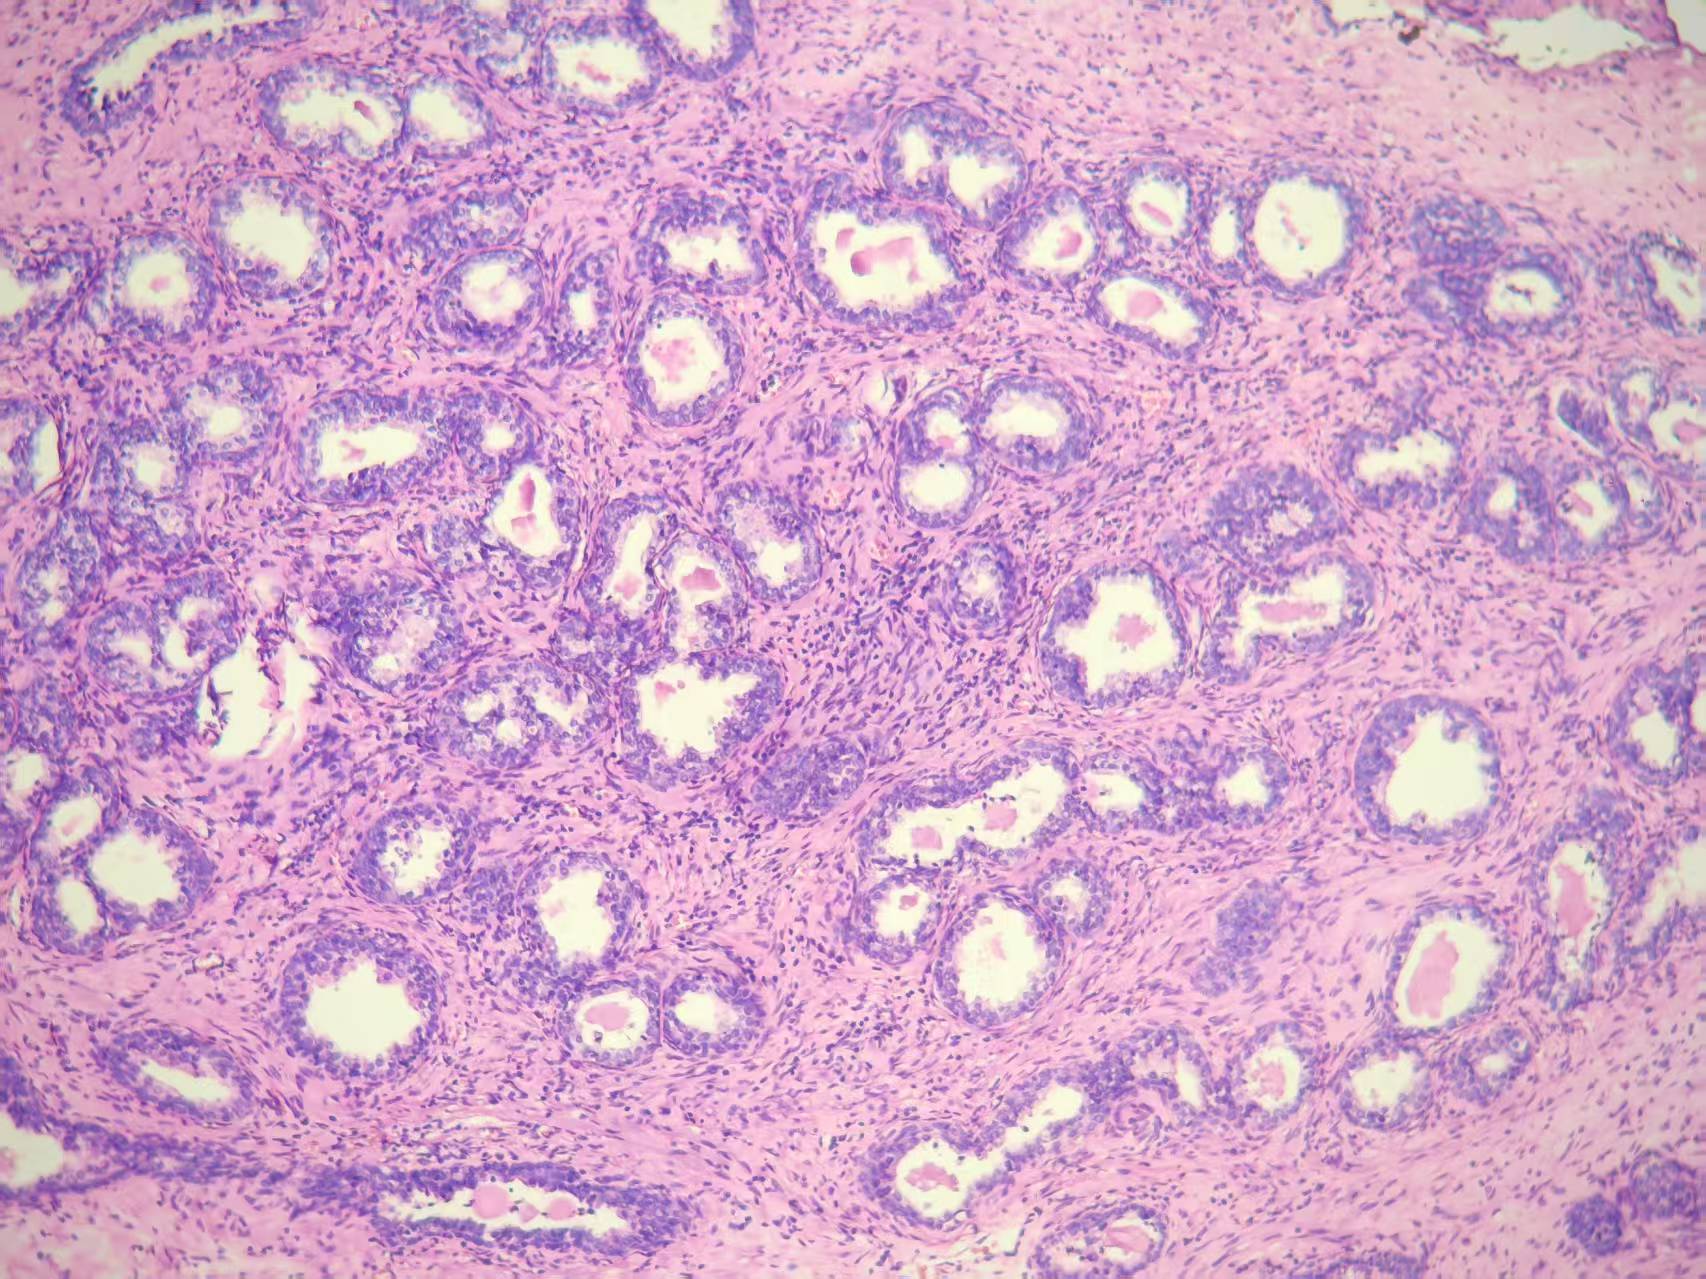

前列腺PIN?

发现肉眼血尿5月余,PAS 5.7

BPH.

本例核仁巨大,值得关注!

嗜酸性大核仁,胞浆透亮,PIN没问题。还是组化一下吧,